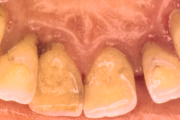

Krooniline parodontiit

Krooniline parodontiit on mikroobide poolt põhjustatud hammaste tugikudede põletik, mille tulemusena tekib progresseeruv alveolaarluu (nähtav röntgenograamil) ja periodontaalligamendi destruktsioon, igemetaskute moodustumine, igeme retsessioon või mõlemad kahjustused kombineeritult. Loe edasi »

- igemepiir on taandunud (3)

- puudulik suuhügieen (5)

- igemepealne hambakivi (5)

- igemealune hambakivi (4)

- hammaste tundlikkus (9)